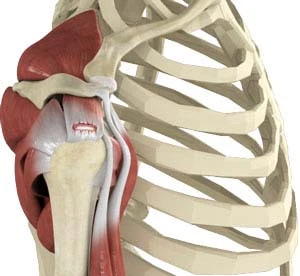

Το στροφικό πέταλο του ώμου σχηματίζεται από την συνένωση τεσσάρων τενόντων του υπερακάνθιου, του υπακάνθιου, του υποπλάτιου και του ελάσσονα στρογγύλου. Από αυτούς εξαρτάται σε μεγάλο βαθμό η ομαλή κίνηση και λειτουργία του ώμου. Ο τραυματισμός ή ρήξη των τενόντων αυτών αποτελεί μια από τις πιο συχνές αιτίες πόνου στον ώμο. Ο τένοντας που υφίσταται συχνότερα ρήξη είναι ο υπερακάνθιος.

Ως ρήξη του στροφικού πετάλου του ώμου ορίζεται η ρήξη ενός ή περισσότερων εκ των παραπάνω τενόντων. Η ρήξη αυτή μπορεί να είναι το αποτέλεσμα είτε ενός οξέος τραυματισμού είτε πολλαπλών μικροτραυματισμών και μακροχρόνιας εκφύλισης, γεγονός στο οποίο συμβάλλει και το σύνδρομο υπακρωμιακής προστριβής. Τέλος μια χρόνια τενοντίτιδα μπορεί να καταπονήσει τον τένοντα, ο οποίος τελικά παθαίνει ρήξη.